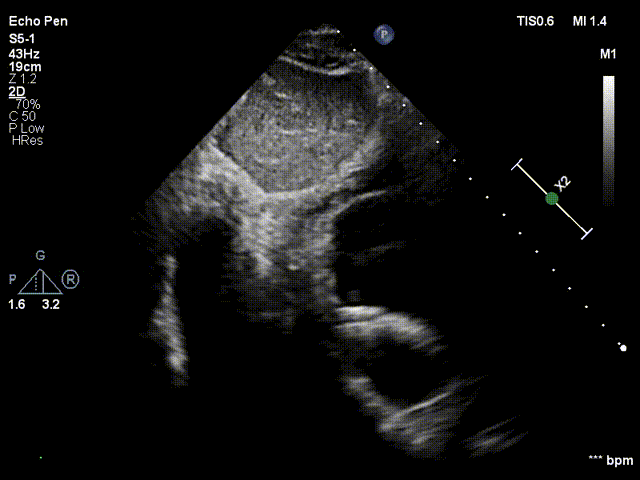

术中分流器形态稳定

食道超声可见左向右分流束